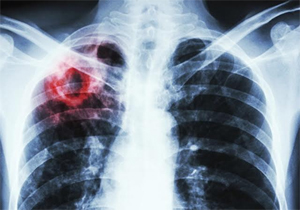

- проведення інструментальної діагностики, зокрема рентгенівських методів візуалізації;

Як зазначила голова Робочої групи за напрямом «Фтизіатрія», кандидат медичних наук С. Дудник, за даними ВООЗ, Україна посідає друге місце у світі за поширеністю туберкульозу з широкою лікарською стійкістю. Зважаючи на актуальність цієї проблеми для України, медичні послуги з діагностики та лікування туберкульозу увійшли до Програми медичних гарантій — переліку послуг, які держава гарантує пацієнту. НСЗУ укладає договори на надання послуг з діагностики та лікування туберкульозу з профільними медичними закладами по всій країні.